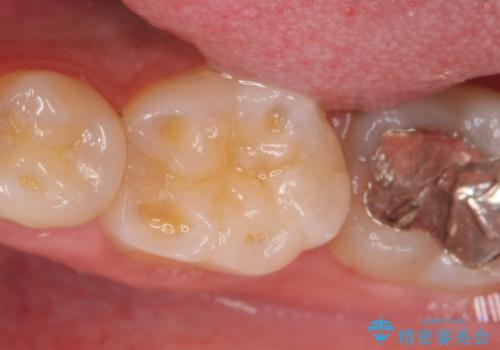

- 左下6の咬耗により歯がしみるている方の症例です。

オールセラミッククラウンによる補綴を行い、症状はなくなりました。